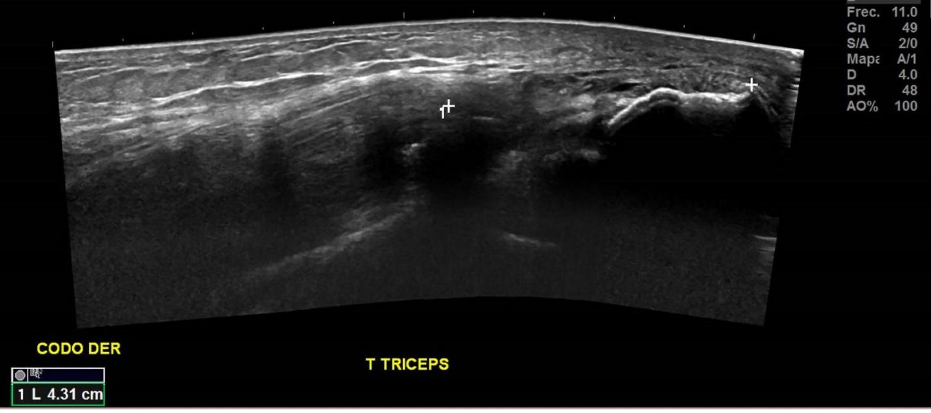

Paciente con antecedentes de fractura avulsiva del olecranon en codo derecho de 1 día de evolución, se presenta con hematoma y aumento de volumen difuso en articulación. Examen se solicita para conocer el porcentaje de compromiso del tendón tricipital.

No se observan fibras del tendón del tríceps a nivel insercional, con fragmento óseo avulsivo en tercio medio del tendón del tríceps, correspondiente a rotura total.

Hallazgos: Tendón tricipital no visualizado en el tercio distal, en el contexto de rotura completa, con gap de 43 mm y fragmento óseo avulsivo en su espesor en el tercio medio, mide 9 mm. Se identificaron extensos cambios inflamatorios a este nivel y aumento de señal al estudio Doppler Color.